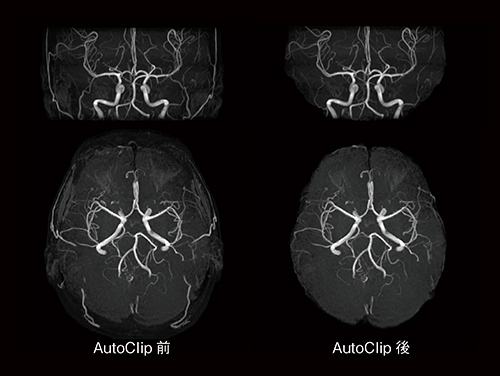

頭部MRAにおいて,頭皮や不要な血管などを削除するのが一般的ですが,日立ではこの作業をクリッピング(Clipping)処理と呼んでいます。クリッピング処理はオペレーターの知識や経験に依存している部分が大きいと言えます。つまりMRAの撮像後,ほかのすべての撮像が終わるまでにクリッピング処理を行い,MIP画像を作成する必要があります。これは操作に慣れたオペレーターであっても大きな負担になっています。AutoClipは,頭部における特徴量に基づいて元画像から脳領域を識別抽出することにより,不要部分のクリッピング処理を実施します。図7は,AutoClip前後のMIP画像を比較したものです。頭皮など不要な部分が自動的に削除されており,明瞭なMIP画像となっていることがわかります。

図7 AutoClip前後の比較(MIP画像)

不要な領域が削除されているのがわかる。